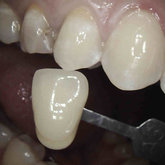

He received his Diploma in Implantology in 2016 from the University of Pretoria, which he passed with Distinction. He is also a member of the International Team for Implantology (ITI), which is based in Switzerland and offers members access to the latest research and cutting-edge techniques.

Porcelain crowns and restorations made in one appointment.

We make it a priority to incorporate the latest in dental technology in everything we do at our practice. ...